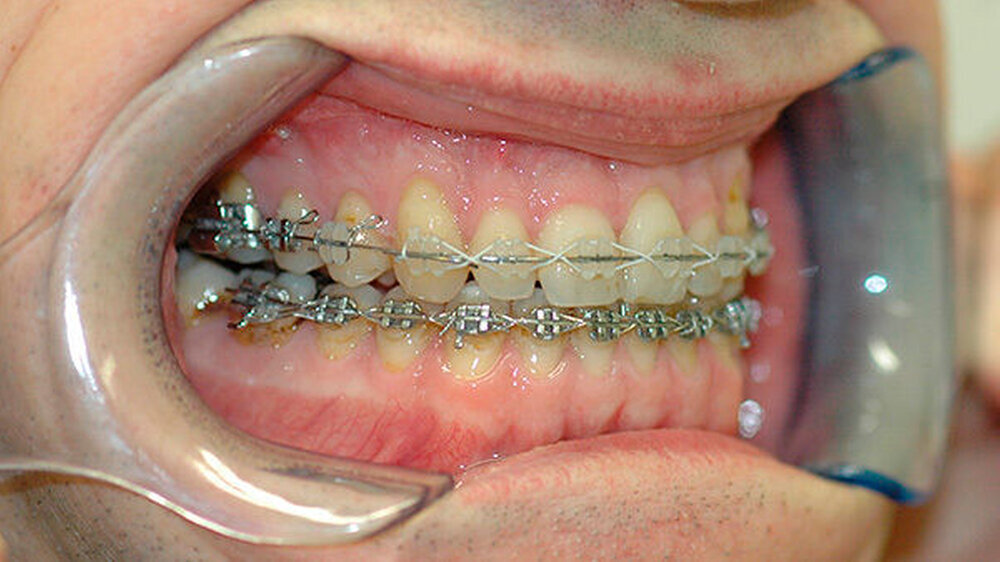

Das deutlich harmonischeres Profil drei Monate nach der Operation: Im Mai des nachfolgenden Jahres wurden die Metallplatten in einem ambulanten Eingriff wieder entfernt. Eine Multibandapparatur hält die Zähne noch "in der Reihe". Der Patient kann heute dank der individuellen innovativen Behandlung ein normales Leben führen, die Gesichtsästhetik und seine Kaufunktion sind vollständig wiederhergestellt.